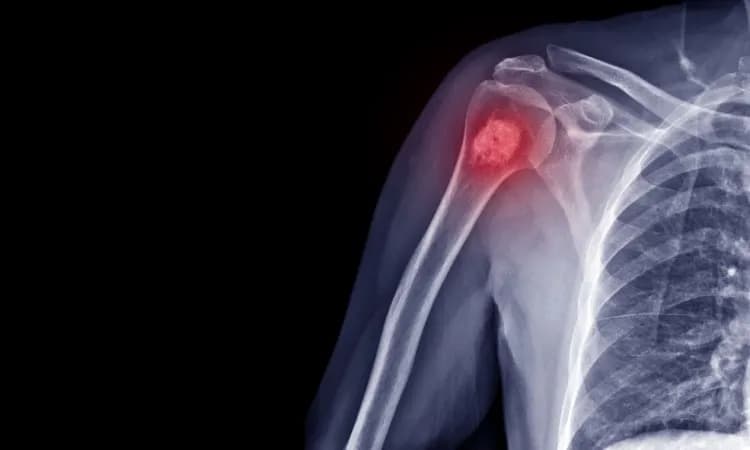

Podstawowym badaniem jest RTG zajętej okolicy, które może ujawnić charakterystyczne zmiany w strukturze kości. Kolejnym krokiem jest wykonanie tomografii komputerowej lub rezonansu magnetycznego. Te badania pozwalają dokładnie określić lokalizację i wielkość guza.

- RTG - podstawowe badanie obrazowe

- Tomografia komputerowa (CT) - szczegółowy obraz zmian

- Rezonans magnetyczny (MRI) - ocena zajęcia tkanek miękkich